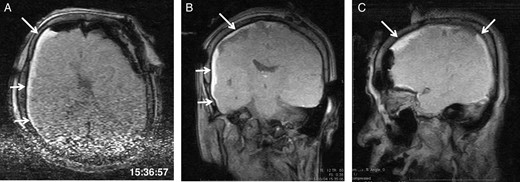

General anaesthesia was induced. Following left frontal craniotomy and dural incision, the first iMRI was performed (Fig. 1 ). One hundred fifty-eight minutes from induction, the patient regained consciousness after all anaesthetics were ceased. Tumour resection was performed with free conversation. However, after 143 min of surgery under the awake condition, the patient came to complain of excessive sleepiness though she could respond to verbal commands. Electrocorticogram (ECoG) did not detect after-discharge. The tumour was successfully removed en bloc fashion. Progressive brain swelling was not observed. The second iMRI was commenced 182 min into the awake phase (Fig. 2). Thirteen minutes from the beginning of the second iMRI scanning, the patient did not respond to noxious stimuli. When the patient was removed from the gantry, she was unconscious and had stopped spontaneous breathing. Her pupils were isocoria and did not dilate. Neither epileptic seizure nor anaphylactic reaction occurred. The peripheral oxygen saturation was not measurable, but cardiac instability or signs of vomiting were not observed. We decided to discontinue the operation under the awake status. No electrolyte imbalance or hypoglycaemia was observed. Subsequently performed iMRI identified a thin subdural haematoma in the contralateral side (Fig. 3). The fourth iMRI confirmed that most of the haematoma was evacuated following right frontal craniotomy.

The second iMRI was performed after the tumour resection. (A) Axial, (B) coronal and (C) sagittal T1-weighted scout images show no intracranial haemorrhage. The time of scan is superimposed.